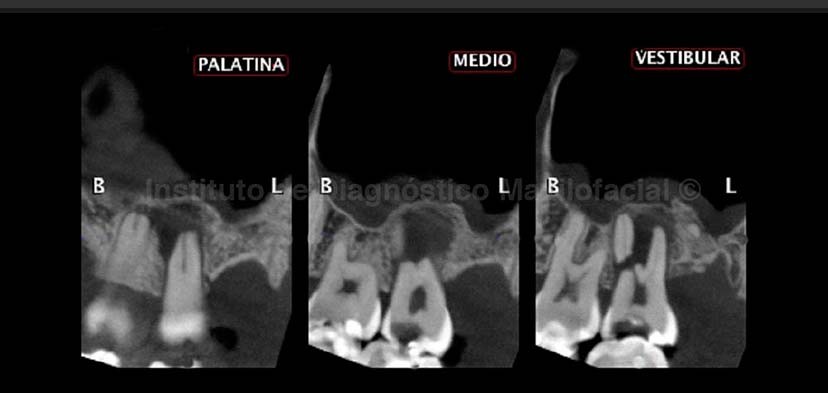

A la evaluación de la radiografía panorámica se observa una lesión de caries oclusal amplia en la pieza 27, además de una radiolucidez difusa a nivel radicular de la misma (Fig 1).